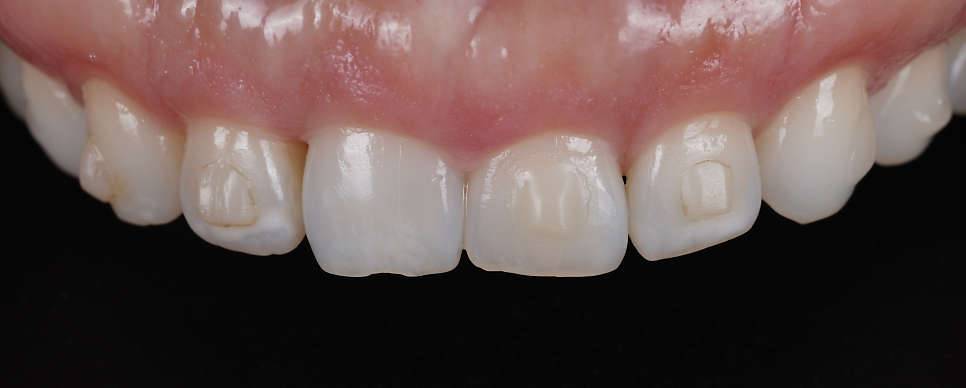

그리고 #12^13 사이에 교정 후 흔히 볼 수 있는

블랙 트라이앵글(잇몸이 꺼지면서 생기는 틈)이

생겼더라고요.

그것도 메워드리기로 했고요.

하방으로 반점치가 있더라고요.

반점치도 레진으로 해결하기로 했습니다.

#11,21 길이 연장

#12 블랙 트라이앵글 메우기

#12,22 반점치 제거

이렇게 계획을 세웠습니다.